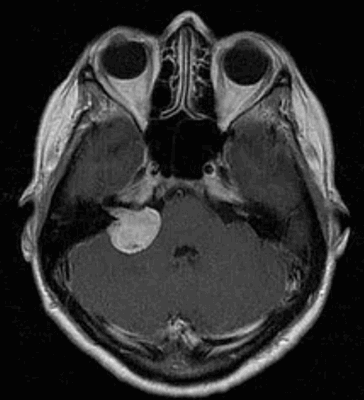

Слева - МРТпациентки М., 65 лет. Обратилась в радиохирургический центр МИБС с диагнозом-невринома правого VIII нерва. Проведено радиохирургическое лечение, доза по краю невриномы составила 13 Грей, в изоцентре опухоли 21,7 Грей.

Справа - контрольное МРТ через 1,5 года после операции. Отмечается уменьшение объёма опухоли на 47%.